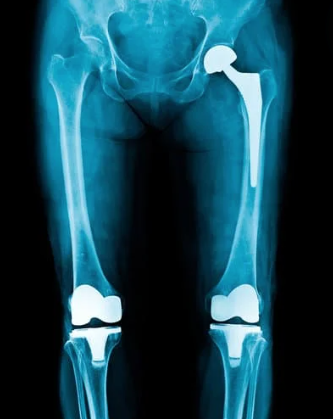

- 接受过研究员培训的专家:莫顿医生接受过髋关节和膝关节重建方面的研究培训,拥有复杂关节翻修方面的专业知识和技能。

- 尖端技术:我们利用骨科手术和医学影像方面的最新进展,包括现场 X 光和金属杂质减少核磁共振成像,提供精确有效的治疗。

髋关节和膝关节翻修诊所

髋关节和膝关节置换手术翻修是必要的,原因有很多,包括

- 种植体松动:随着时间的推移,骨与种植体之间的粘结力会减弱,从而导致疼痛和不稳定。

- 感染:植入区域周围的感染会导致严重的并发症,因此必须进行翻修手术,移除并更换受感染的组件。

- 假体磨损:随着时间的推移,假体部件可能会磨损或损坏,需要更换以维持功能。

- 脱位:在髋关节置换术中,植入物有时会脱位,导致疼痛和活动受限。

- 骨折:植入部位周围的骨折会影响关节置换的稳定性。

- 持续疼痛:初次置换手术后疼痛无法缓解,可能表明需要进行翻修手术。

- 腿长不一致:初次手术后腿长不一致会导致不适和功能问题。

- 僵硬和关节纤维化:活动范围受限和关节僵硬可能需要进行翻修手术。

- 异位骨化:关节周围异常的骨质增生会损害关节功能并导致疼痛。